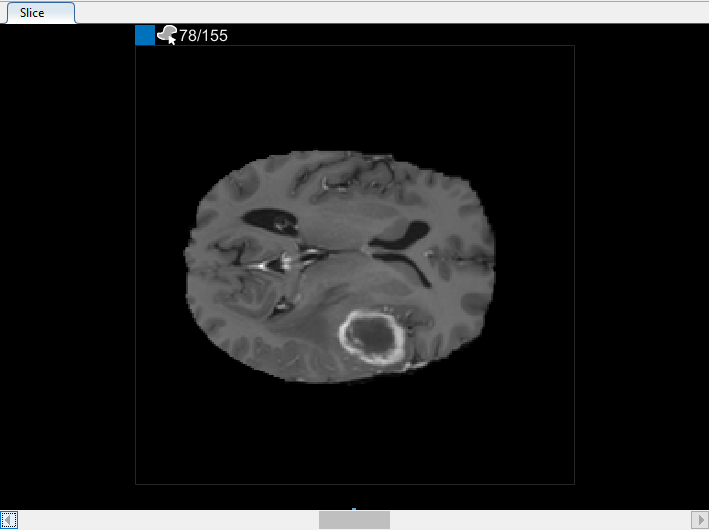

В панели Среза перейдите к срезу, где объект сначала появляется, и начните помечать объект на каждом срезе с помощью инструмента для рисования. В следующем рисунке этот пример использует инструмент Paint Brush, чтобы пометить опухоль. Как ранее, можно чертить объект на каждом срезе, где это появляется, или используйте инструменты интерполяции, чтобы привлечь несколько срезов автоматически. После интерполяции можно использовать инструменты для рисования, такие как Средство стирания, чтобы изменить автоматизированную сегментацию на каждом срезе.